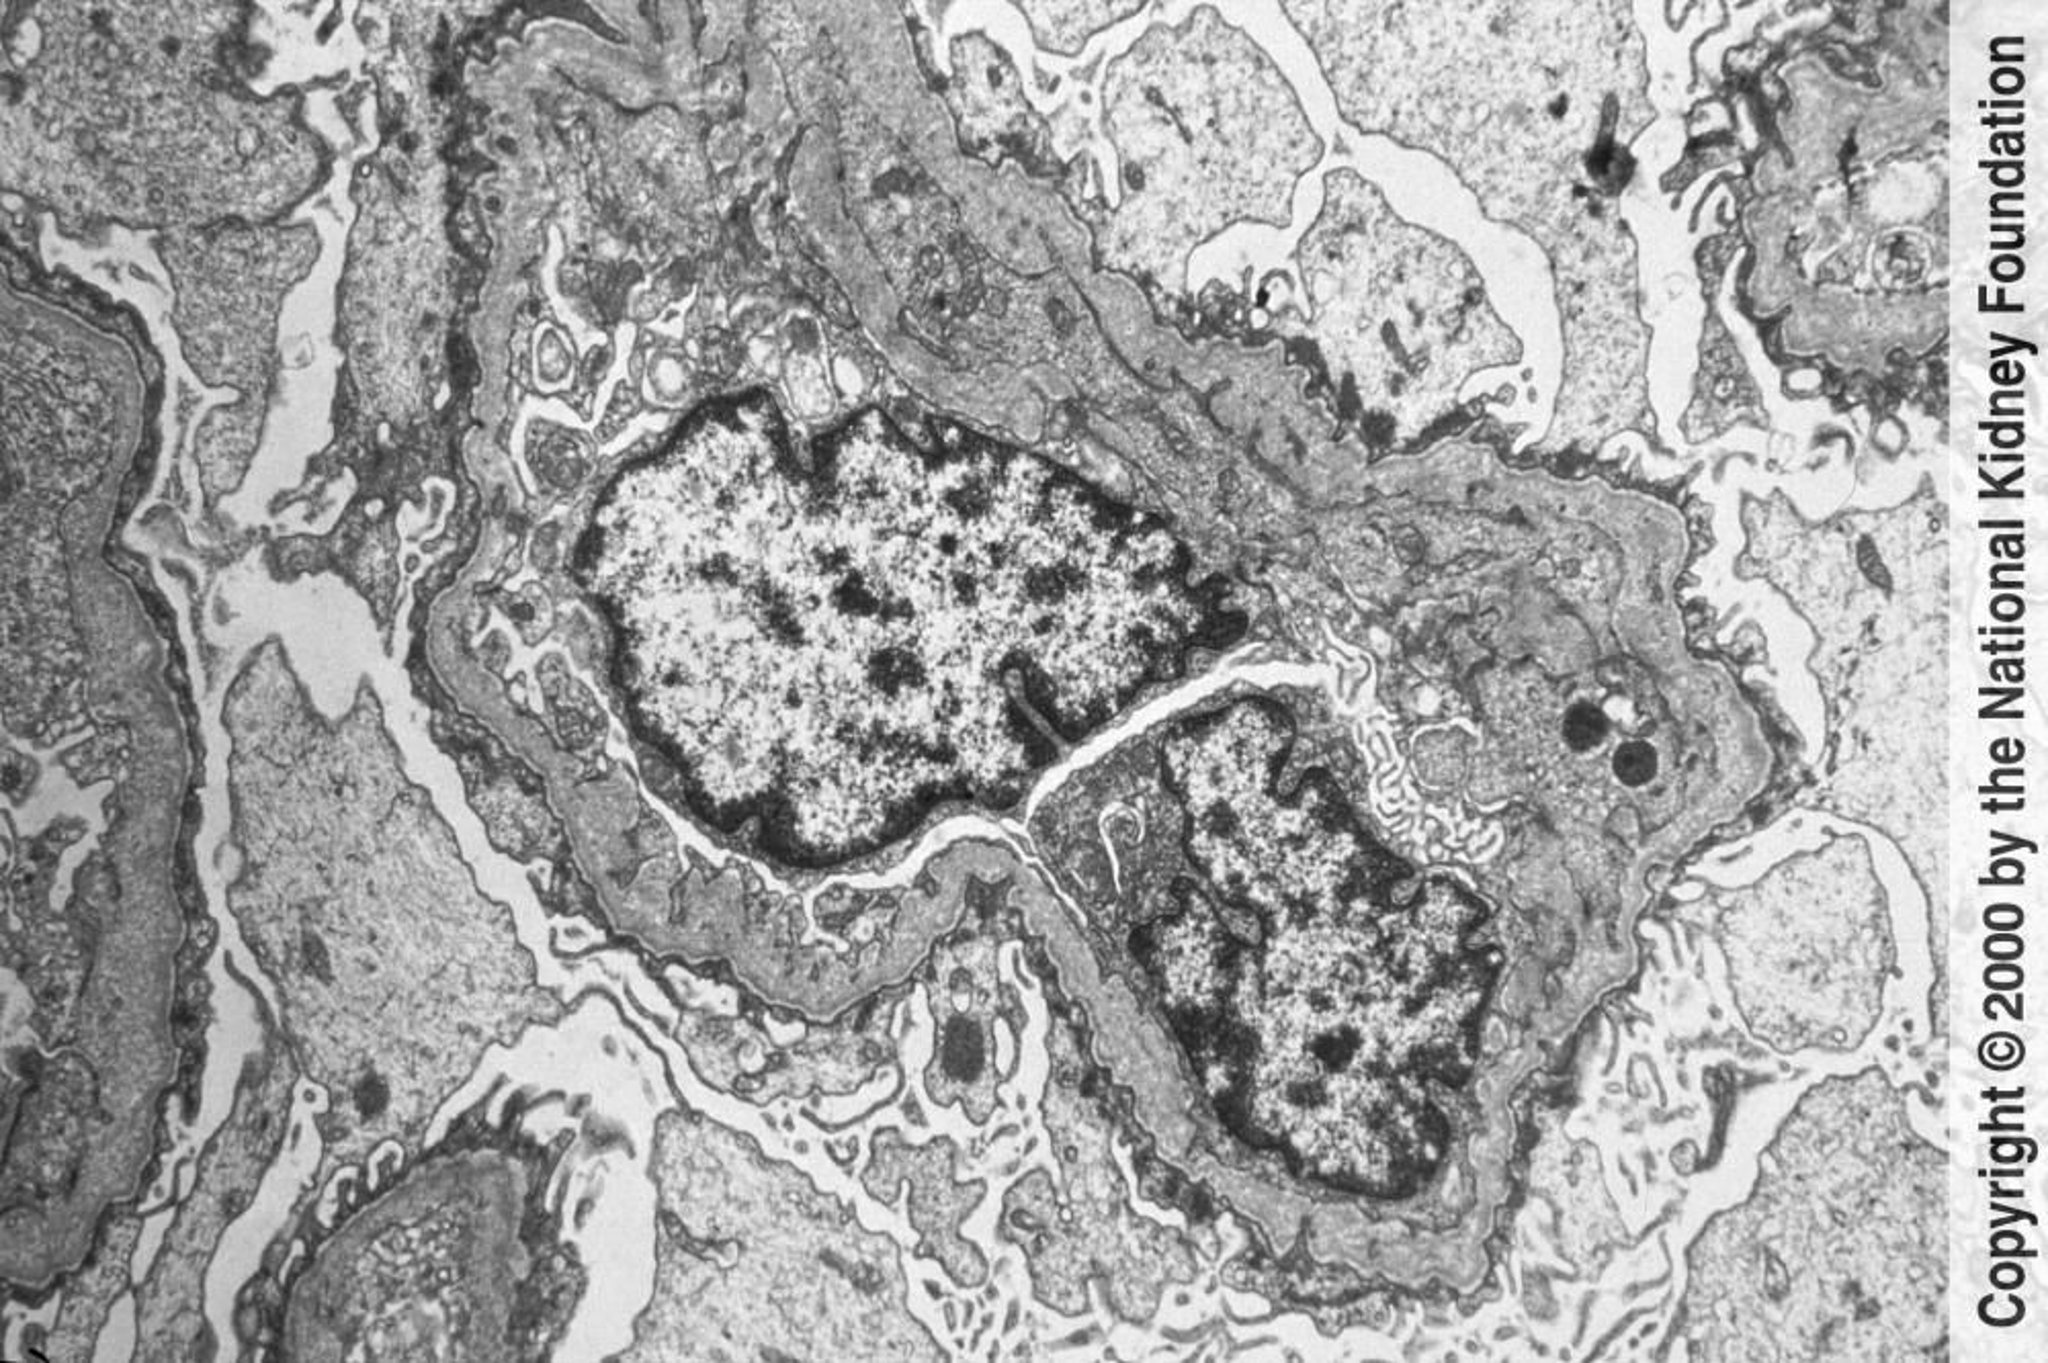

Sindrome di Alport (nefrite ereditaria)

Le membrane basali glomerulari in la microscopia elettronica a trasmissione mostrano assottigliamenti e ispessimenti irregolari con aspetto a trama di cesto. I cambiamenti sono causati dai danni e dal rimodellamento (×6000).

Imagine fornita da Agnes Fogo, MD, and the American Journal of Kidney Diseases' Atlas of Renal Pathology (vedi www.ajkd.org).